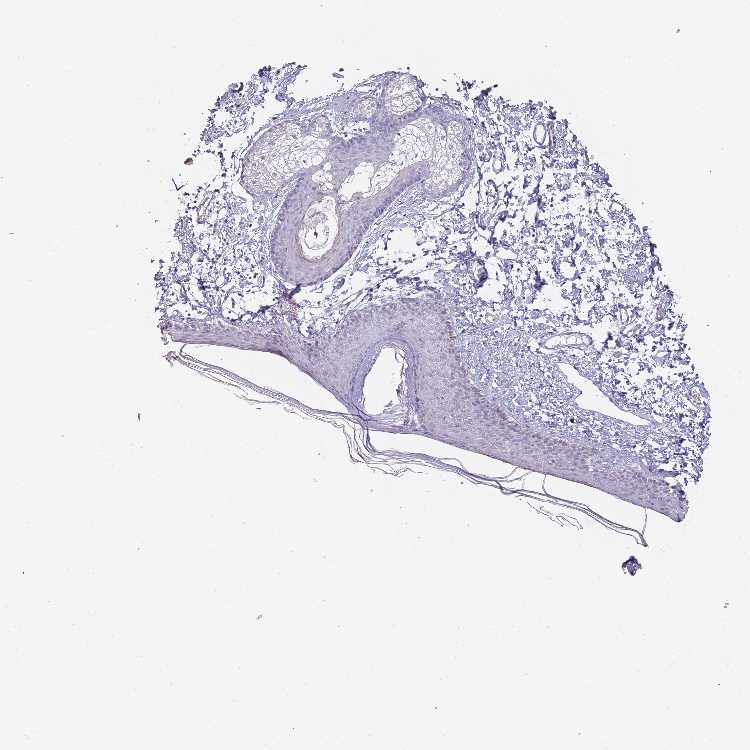

SKIN 1 - Antibody stainingi

Antibody staining in the annotated cell types in the current human tissue is reported as not detected, low, medium, or high, based on conventional immunohistochemistry profiling in selected tissues. This score is based on the combination of the staining intensity and fraction of stained cells.

Each image is clickable and will lead to virtual microscopy that enables deeper exploration of all samples and also displays staining intensity scores, fraction scores and subcellular localization as well as patient and tissue information for each sample.

Antibody HPA037763Antibody HPA037764Antibody CAB026170

Langerhans Not detectedNot detectedLow

Fibroblasts Not detectedNot detectedNot detected

Keratinocytes Not detectedNot detectedLow